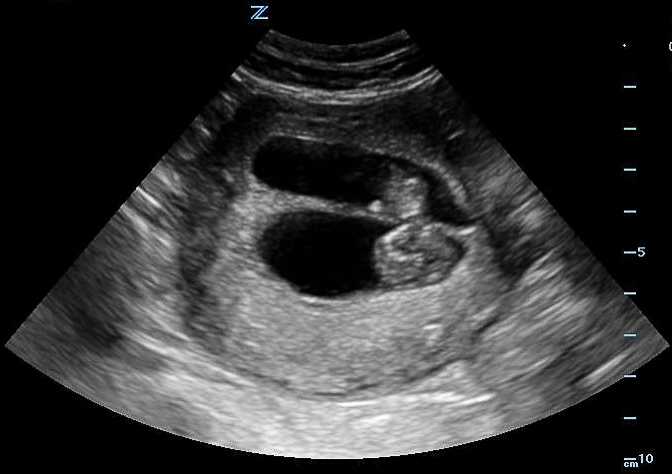

- Mechanical Risk Factors for Delivery

Figure 29. Transverse suprapubic view revealing the fetal cranium in the pelvis, consistent with a vertex presentation. Note the calipers measuring a bi-parietal diameter at 30 weeks and 6 days.

- Non-vertex (breech, transverse, or oblique) increases risk of difficult delivery and complication25

Figures 30A & B. Suprapubic views revealing no fetal cranium in the pelvis. While in some cases like this transverse view of a breech presentation (A) and this sagittal view of a transverse presentation (B), it may be difficult to exactly determine the fetal anatomy, the lack of the fetal cranium is adequate to rule out a vertex presentation and should increase the clinician’s suspicion for a more difficult delivery.